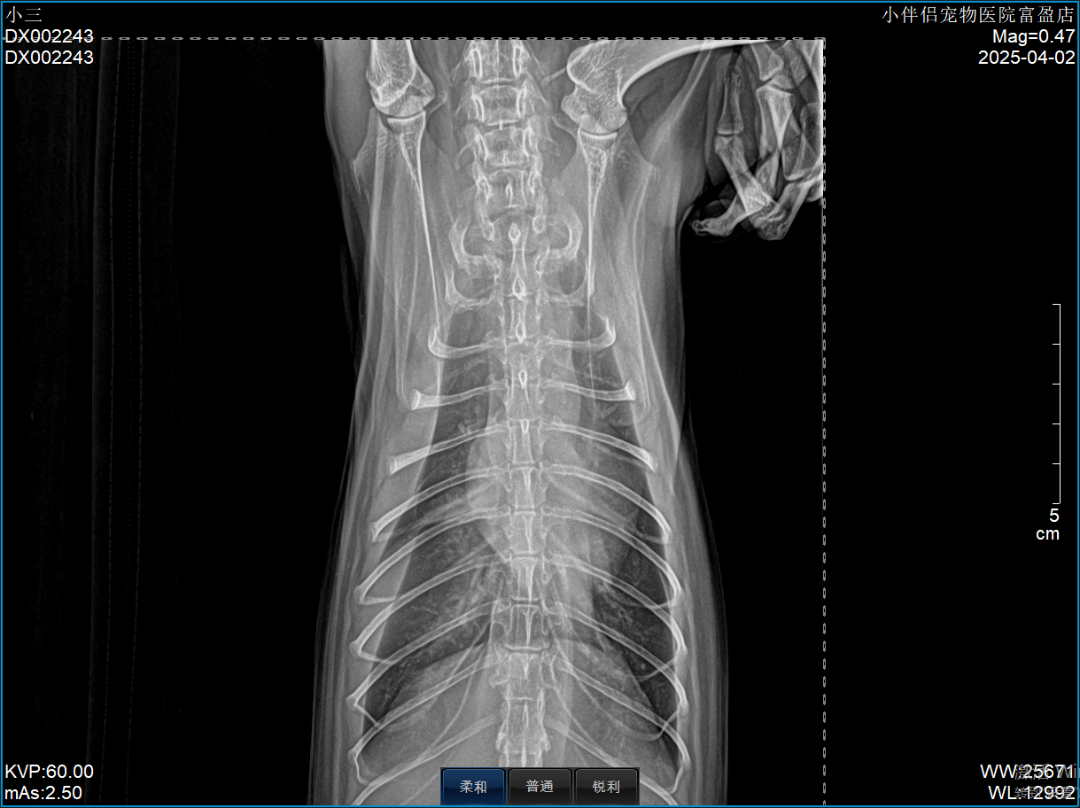

在尿闭治疗第五天,猫咪突然出现呼吸急促、咳嗽症状,因其有家族心脏病史,遂进行X光、心超、BNP、鹏佑猫肥厚型心肌病核酸检测,结果如下:

4.2X光.png

(肺水肿)